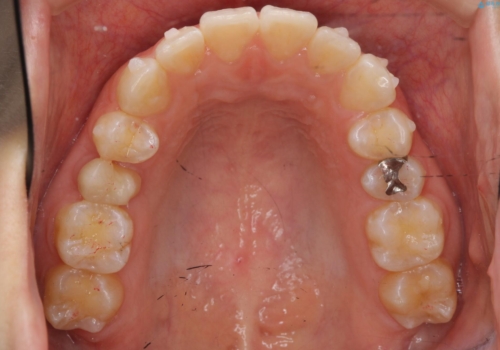

- 前歯のがたつきを治したいとのことでした。歯を抜かずにできる範囲で引っ込めたいとのことでした。

歯列の側方拡大(横に広げる)と、エナメル質の削合で並べました。

右上4番目の被せ物の治療については以下で紹介しています。